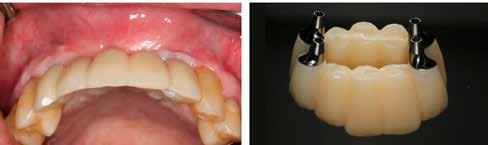

Dr. Gáspár Lajos

RÖVID ÉS KESKENY IMPLANTÁTUMOK AKTUÁLIS KONSZENZUS KÉRDÉSEI

A XXI. század fogászatának egyik legdinamikusabban fejlődő ágazata a fogászati implantológia, napról napra újabb és újabb kérdéseket, kihívásokat jelent, melyekre újabb és újabb, ma már konszenzuson alapuló válaszok születnek. Ezek nagyban segítik a gyakorló orvosokat a helyes és biztonságos megoldások kiválasztásában, a rizikó csökkentésében, továbbá a kiszámítható, minél kevésbé invazív eljárások alkalmazásában. Ez az iránymutatás és ezek megerősítése meghatározó jelentőségű a szakma fejlődése és tudományos megalapozottsága szempontjából.

1. ábra: Dr. Jung 10 éves kontrollal rendelkező 4.7-es helyén levő Dentium short implantációja. Preoperativ CT, ínyformázó 4 hónappal a műtét után, valamint 4 hónap múlva 4.7-es szólókorona.

2. ábra: Dr. Park esete. 4.6-os fogon levő jelentős csontfelritkulás röntgenképe, extractio és iGBR alkalmazása Osteon Xenoval. 4 hónap múlva Dentium short implantátum, majd 4 hónap múlva korona készítése.

Dr. Park Jung Chul, a szöuli Katolikus Egyetem előadója a páciens és orvos-barát megoldásként alkalmazott, nyitott gyógyulású iGBR technikával foglalkozott. Egyik esetében a jobb alsó 6-os fogon periapicalis léziót mutatott be, majd extractio, iGBR alkalmazása, és 4 hónappal később implantáció, továbbá korona készítése történt.

3. ábra: Dr. Han esete. 2.4-2.5-2.6 lokalizációban keskeny gerinc. Csontpótlás Osteon Xeno- val, majd 4 hónap múlva 3 db Dentium short implantátum behelyezése. 4 hónappal később protetikai munka.

5. ábra: Dr. Chun esete. Dentium Narrow implantátumok és azok protetikai ellátása 4 hónappal a beültetést követően.

6. ábra: Dr. Lim esete. Dentium Narrow implantátumok a felső állcsonton, guide tervezés, ideiglenes hídpótlás azonnali terheléssel, majd 4 hónappal később végleges protetikai ellátás.

A Dentium cég elnöke, dr. Chung Sung Min a „Minimalizmus rövid és keskeny implantátumokkal” címmel tartott előadást. Kiemelte, hogy mind az alsó, mind a felső állcsonton elsősorban a moláris régióban találkozunk alacsony gerinccel, ahol a short implantátumok ma már igazoltan jó, biztos és bevált megoldást jelentenek. Ezzel már több mint 10 éves tapasztalatok állnak rendelkezésre, és konszenzus alakult ki az alkalmazásuk feltételeiről, melyben az ITI nemzetközi ajánlásait tartja a Dentium is követendőnek.

Dr. Chun hangsúlyozta a felső és alsó frontterület gyakori keskeny gerincét, ahol kedvezően alkalmazhatóak a keskeny implantátumok.

Dr. Chun kiemelte, hogy a rövid és keskeny implantátumok alkalmazása ma már forradalmasította az implantológiát, és újragondolásra késztette a klasszikus definíciókat. Fontos minden esetben a könnyebb, egyszerűbb, biztonságosabb, költséghatékony megoldások keresése. A Dentium implantátumok

7. ábra: Dr. Byun esete. Keskeny állcsontgerinc a jobb alsó és mindkét oldali felső laterális régióban. Implantáció Dentium Narrow implantátumokkal, majd 4 hónap múlva protetikai ellátás.

8. ábra: Dr. Chang esete. 2.4-es fog helyén keskeny gerinc. Csontpótlással együtt Dentium Narrow implantátum behelyezése. 4 hónap múlva korona készítése.

fejlesztése az ITI irányelvek figyelembevételével történik, és mind a rövid, mind a keskeny implantátumok területén lehetőséget nyújtanak ezek biztonságos alkalmazására.

Dr. Lim Sang Chui, a Szöuli Egyetem parodontológusa előadásában a digitálisan, guide segítségével keskeny gerincbe történő implantáció módszerét mutatta be. Elmondta, hogy világszerte elfogadott a minimálisan invazív módszerek alkalmazása, és különösen a keskeny állcsontgerinc esetén nagy jelentősége van a guide módszernek.